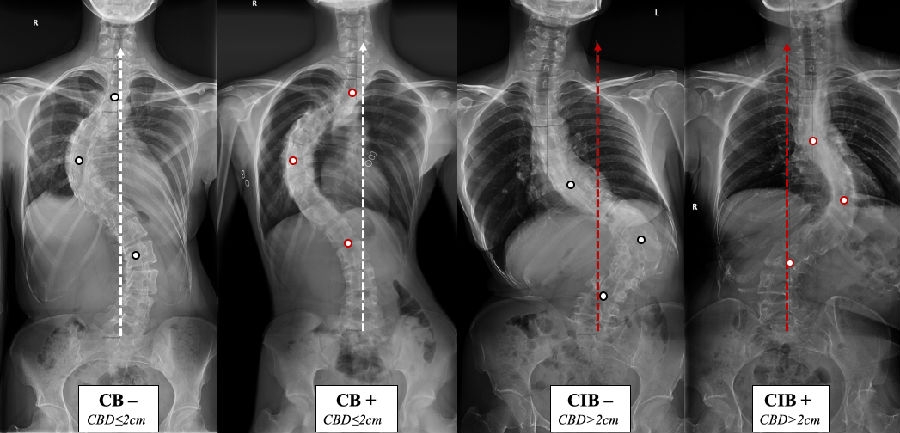

五、顶椎位置修正对手术矫形方案的指导意义

(1)术前CB患者,对称矫形:主弯矫正幅度=代偿弯矫正幅度之和。

(2)术前CB-患者,重点矫正主弯,主弯矫正幅度>代偿弯矫正幅度之和。

(3)术前CB+患者,重点矫正腰骶代偿弯,主弯矫正幅度<代偿弯矫正幅度之和。

图8. 各类型患者的手术矫形策略。

(1) 术前CB-患者:主弯矫正70°,上胸弯及腰弯矫正分别为21°和49°,术后维持平衡状态。

(2) 术前CB+患者:主弯矫正83°,上胸弯及腰弯矫正分别为45°和38°,术后维持平衡状态。

(3) 术前CIB-患者:主弯矫正61°,上胸弯及腰弯矫正分别为33°和21°,术后平衡改善。

(4) 术前CIB+患者:主弯矫正61°,上胸弯及腰弯矫正分别为26°和44°,术后平衡改善。